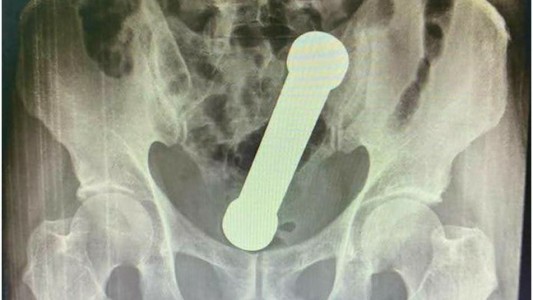

No podía orinar y lo que encontraron en su vejiga sorprendió a los médicos: “Lo hacía por placer sexual”